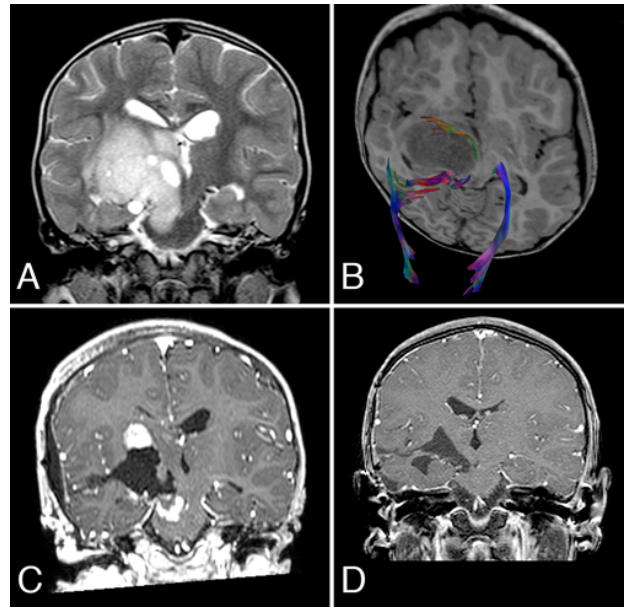

胶质母细胞瘤(GBM)是成人常见的恶性脑肿瘤,许多在较初治疗后几个月内复发,并在2年内出现致命进展。在使用5-氨基乙酰丙酸的荧光、神经导航和术中磁...

小儿丘脑肿瘤常被认为是无法手术的。但是,现代显微外科技术以及神经影像学的改进使得能够进行准确的术前计划,可以以更顺利的方式进行切除...